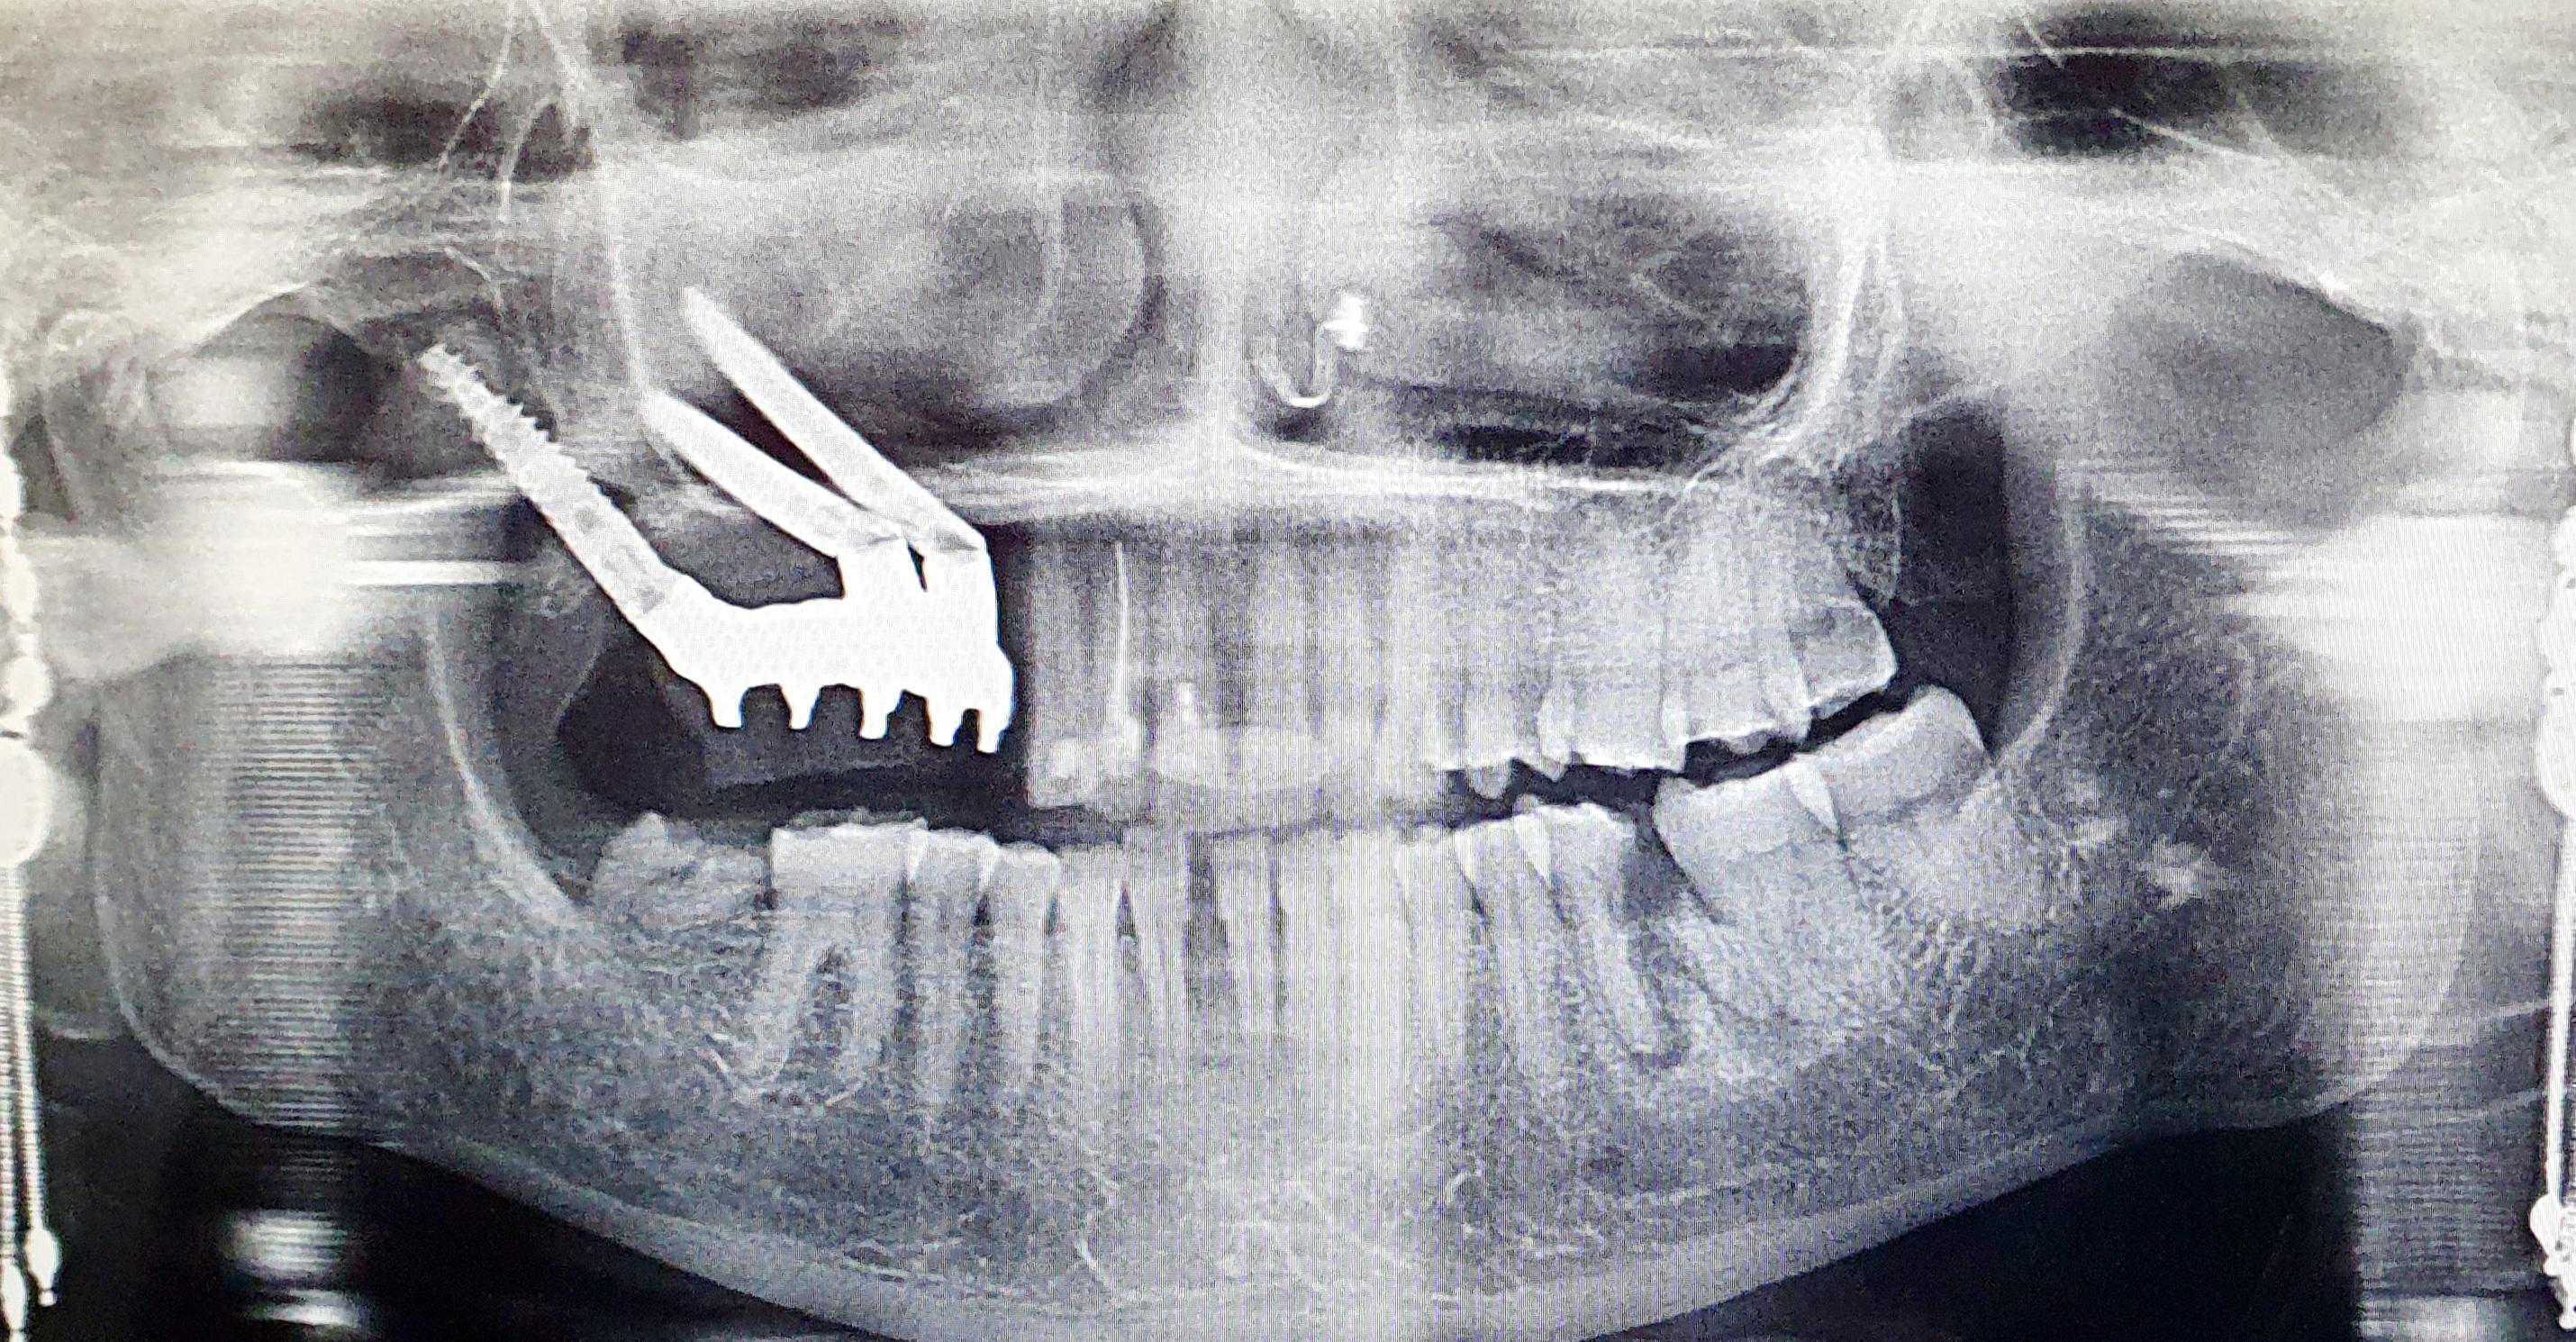

https://demo.discussdentistry.com/forums/topic/post-mucormycosis-avascular-necrosis-of-maxilla-rehabilitation-with-zygomatic/#post-24499 <![CDATA[Post Mucormycosis Avascular necrosis of maxilla, rehabilitation with Zygomatic]]> https://demo.discussdentistry.com/forums/topic/post-mucormycosis-avascular-necrosis-of-maxilla-rehabilitation-with-zygomatic/#post-24499 Thu, 25 Aug 2022 12:14:40 +0000 Sankalp Mittal

• 20210604_101325 (2)20210604_101317 (2)20210604_103315 (2)20210604_102857 (2)20210604_104202 (2)20210604_104853 (2)20210824_105656 (2)20210824_112353 (2)20210824_114957 (2)20210824_131302 (2)20210826_100648 (2)20210826_100749 (2)20210826_100919 (2)20210914_183943 (2)20211001_17535220211012_18543620211012_192043 (2)20211012_185627 (2)20211012_195430 (3)20211027_193725 (2)20211027_200729 (2)20211027_200919